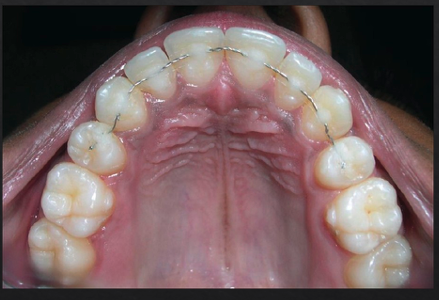

splinting of teeth

what are some indications for splinting teeth?

For patient comfort on mobile teeth

Pathologic tooth migration

Guided tissue regeneration on mobile teeth

Prosthetics where multiple abutments needed

what is a prerequisite to splinting?

control of periodontal inflammation

t/f: splinting itself induces periodontal regeneration

false. Splinting only mechanically stabilizes teeth, it does NOT by itself induce periodontal regeneration